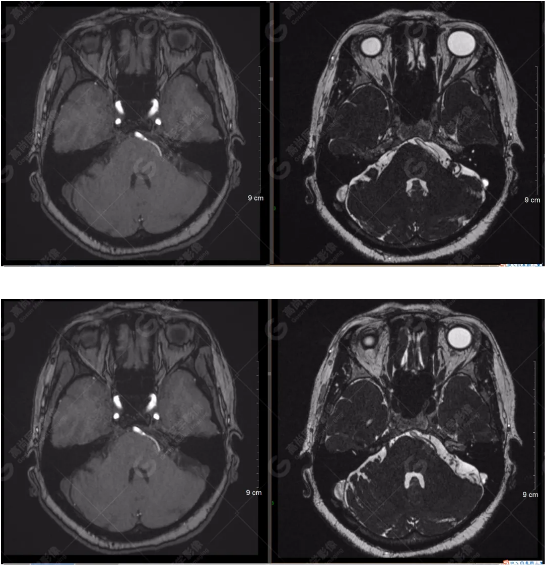

雙側(cè)大腦半球?qū)ΨQ,灰白質(zhì)對比正常,右側(cè)顳部見一囊狀長T1長T2信號影,F(xiàn)LAIR序列呈低信號;余腦實質(zhì)內(nèi)未見局灶性信號異常。各腦室、腦池大小、形態(tài)均正常,中線結(jié)構(gòu)居中,幕下小腦、腦干無異常。矢狀面示垂體大小形態(tài)正常,未見局灶性信號異常。

顱腦MRA及ciss序列示腦基底動脈環(huán)完整,雙側(cè)頸內(nèi)動脈末段、大腦前動脈、大腦中動脈、大腦后動脈及其主要分支顯影良好,管徑及走行正常,無明顯局灶性增粗或變細(xì)。雙側(cè)椎動脈末段沿延髓左側(cè)向上走行,左側(cè)面聽神經(jīng)輕度受壓移位,左側(cè)面聽神經(jīng)周圍見細(xì)小血管包繞。右側(cè)面聽神經(jīng)及雙側(cè)三叉神經(jīng)周圍未見異常血管影。

1.雙側(cè)椎動脈末段沿延髓左側(cè)向上走行,左側(cè)面聽神經(jīng)輕度受壓移位,左側(cè)面聽神經(jīng)周圍見細(xì)小血管包繞,可符合面聽神經(jīng)壓迫綜合征。

2.右側(cè)顳部蛛網(wǎng)膜囊腫。